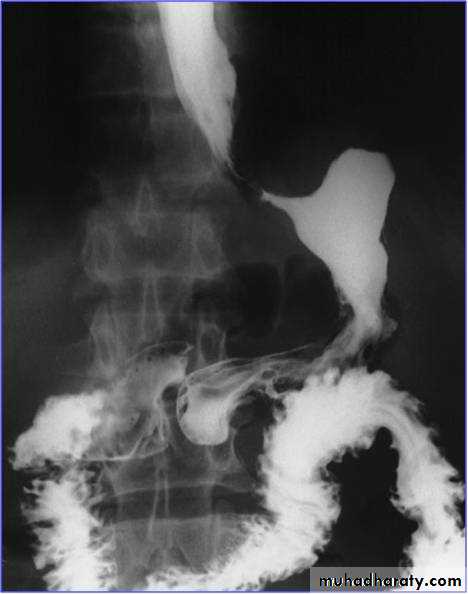

Barium meal: is a poor alternative.

Linitis plastica

The underlying cause is usually a scirrhous adenocarcinoma with diffuse submucosal infiltration, leading to thickening and rigidity to the stomach wallLocation: 50% in the antrum, 20-30% occur in the gastric body, 20% in the cardia, or diffuse submucosal infiltration (uncommon).